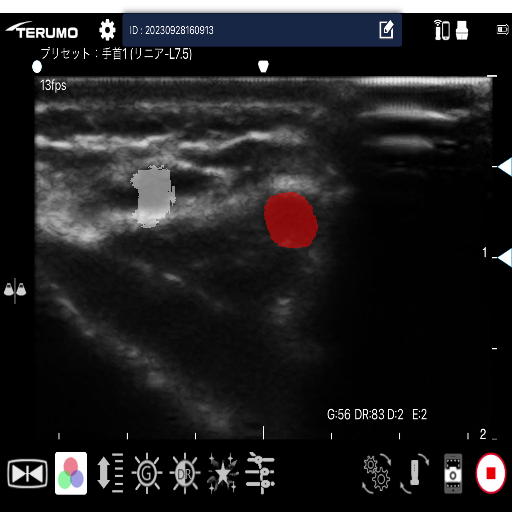

医療現場において、エコー穿刺等の手技によって超音波動画像が活用されています。エコー穿刺は、穿刺部位に超音波を当て、動画像からリアルタイムで血管の位置を確認しながら、動脈もしくは静脈に穿刺を実施する方法です。

しかし、超音波動画像は不明瞭な上、動脈と静脈の見分けを時系列的な血管の形状変化で判断する必要があり、熟練者でなければ判断が難しい現状があります。

現在、動脈及び静脈を含む超音波動画像から動画像解析を活用した機械学習モデルの学習・推論を行い、その分類精度の評価を行なっています。

超音波動画像からの動脈・静脈検出